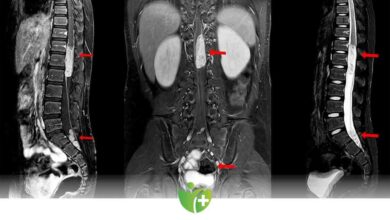

Sırt Ağrısı Omurga Tümörü habercisi olabilir

Sırt ağrısı, omurga tümörleri gibi ciddi sağlık sorunlarının bir belirtisi olabilir. Omurga tümörleri genellikle nadir görülen ancak ciddi sonuçlara yol…